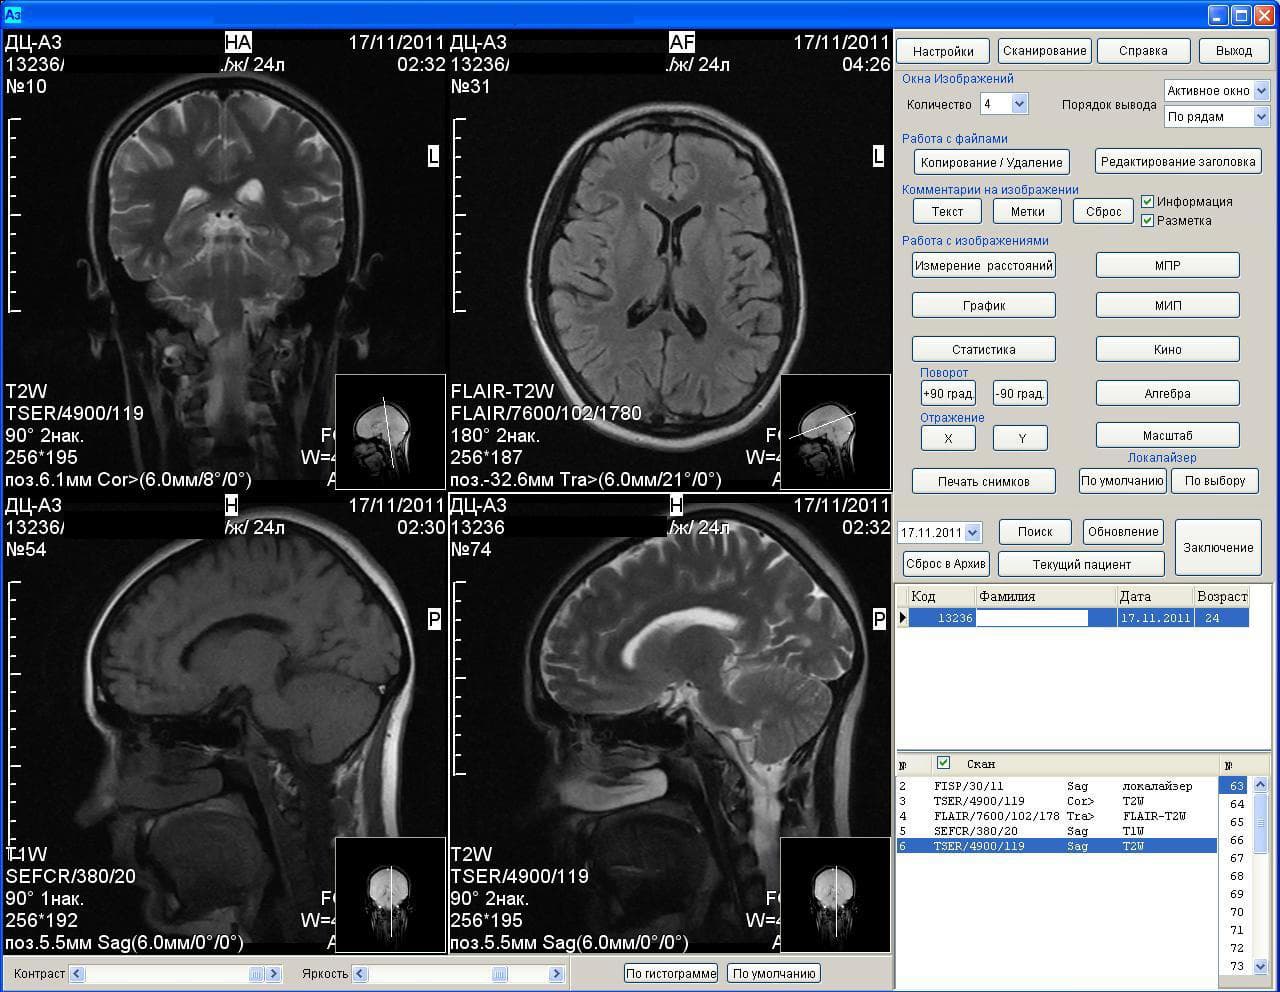

Результаты аппарата МРТ Аз-300

Отмечается, что ученые восстановили функциональные сети головного мозга здоровых людей и пациентов с депрессией. Методика, получившая название «консенсусный подход», выявила различия в результатах функциональной МРТ у двух групп людей.